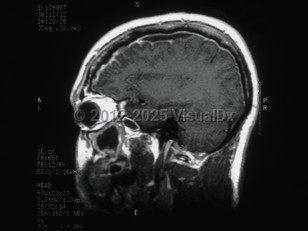

Subdural empyema is a collection of pus in the space between the dura and the arachnoid. Infection of the paranasal sinuses is a risk factor for cranial subdural empyema, as the infection can spread to the space by way of emissary veins. Contiguous spread of infection from osteomyelitis of the skull, meningitis, mastoiditis, or otitis media are also possible. Other etiologies include trauma, seeding of an existing subdural hematoma, or postoperative infection. These infections are typically polymicrobial.

Hematogenous seeding of the space is more likely to result in spinal subdural empyema. This location is less common, accounting for less than 5% of subdural empyema. Staphylococcus aureus is often implicated in infections in this location. Patients may present with fever, headache, and altered mental status (or some combination of these symptoms). Focal neurological signs and seizures may also be present. Magnetic resonance imaging (MRI) with contrast is the diagnostic test of choice.

Treatment is with a combination of surgical decompression and antibiotic therapy. Complications include cerebritis, cerebral abscess formation, and venous sinus thrombosis. Morbidity and mortality in subdural empyema is directly related to delay in therapy.